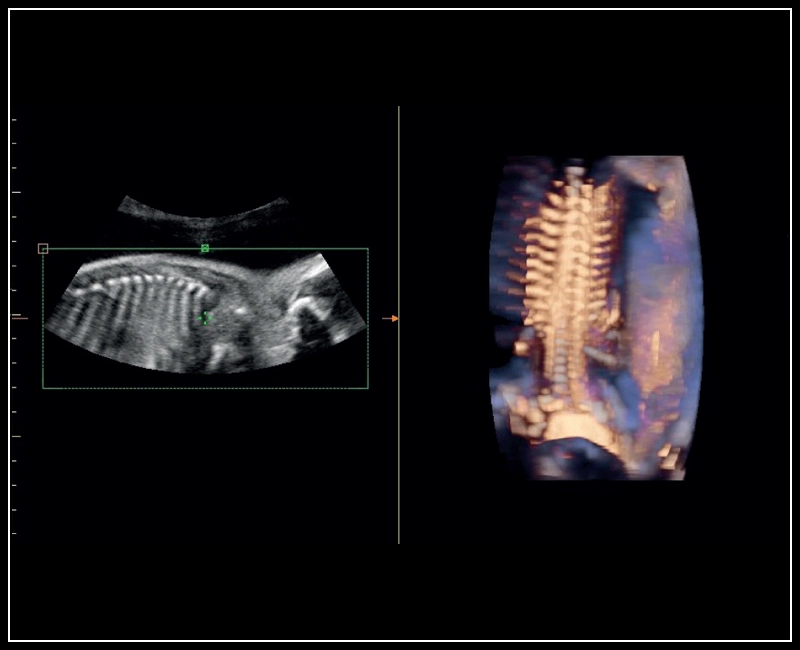

MyLab™Sigma - Semi transparent rendering of fetal spine

MyLab™Sigma - Semi transparent rendering of fetal spine